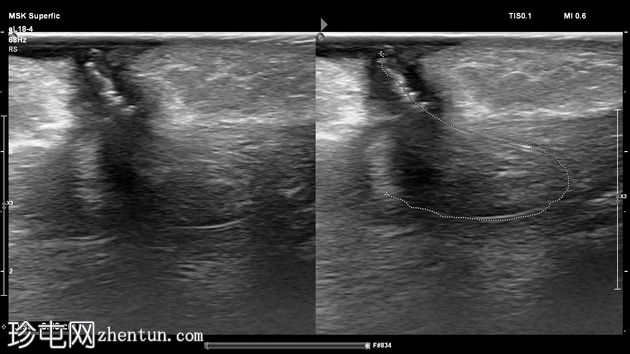

斜位

左足跟皮下组织内可见一管状高回声物质,呈串珠状,与手术缝线相符,周围环绕着低回声积液。与缝线相连的是一根细细的、呈轨道状的高回声合成单丝,它穿过跟腱呈弧形走行,该缝线为不可吸收缝线。